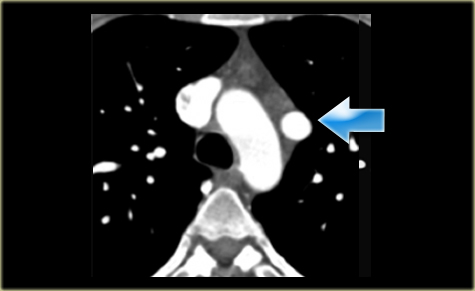

Describe the images on the left and then continue reading.

On the left side there is a vascular structure, that runs inferiorly below the level of the left hilum and enters into a dilated coronary sinus.

The diagnosis is left or double superior vena cava.

Left Superior Intercostal Vein.

This is an anastomosis between the accessory hemiazygos vein and the left brachiocephalic vein.

It courses along the lateral margin of the aortic arch (‘aortic nipple’).

It is a normal variant and if you look for this structure you will frequently notice it.

On the left a patient with a left superior intercostal vein.

Notice the ‘aortic nipple sign’.

On the left another example of a left superior intercostal vein.

It courses along the lateral margin of the aortic arch from the the accessory hemiazygos vein to the left brachiocephalic vein.